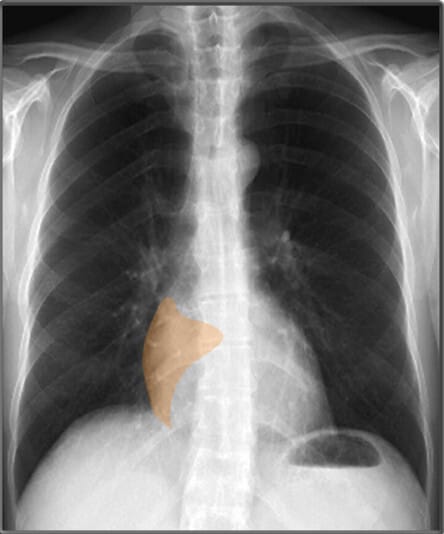

| 위 기포 (Gastric Bubble) |

| ✅ 좌측 횡격막 아래에서 나타나는 공기음영으로, 정상적인 해부학적 지표 중 하나입니다. 위치가 변하면 장폐색 등 복부 문제를 의심할 수 있습니다. |